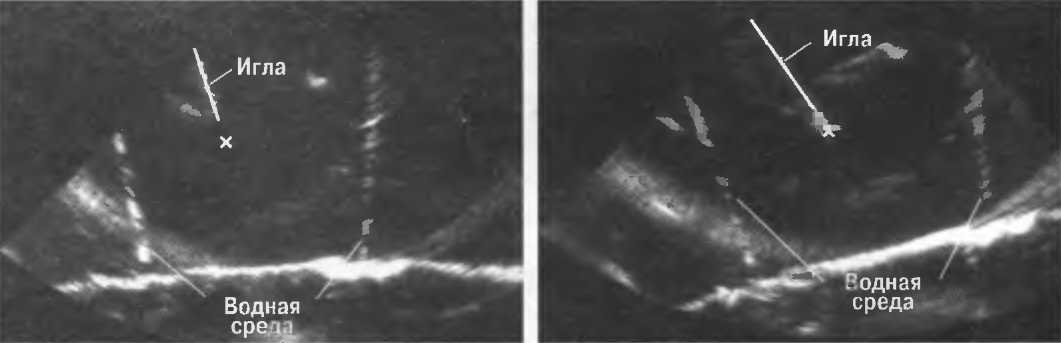

На практике, наиболее значимые в клиническом плане артефакты возникают при проведении биопсии или аспирации под контролем ультразвука. До тех пор пока кончик иглы не появится в плоскости сканирования на экране, он не будет визуализироваться, и может создаться ложное представление о том, что игла значительно короче (рис. 21в).

Рис.21 в. Изображение иглы в емкости с водой. Слева игла находится в плоскости сканирования не полностью, в результате чего выглядит короче, чем есть на самом деле (крестик определяет реальную глубину проникновения иглы). Справа игла визуализируется полностью.